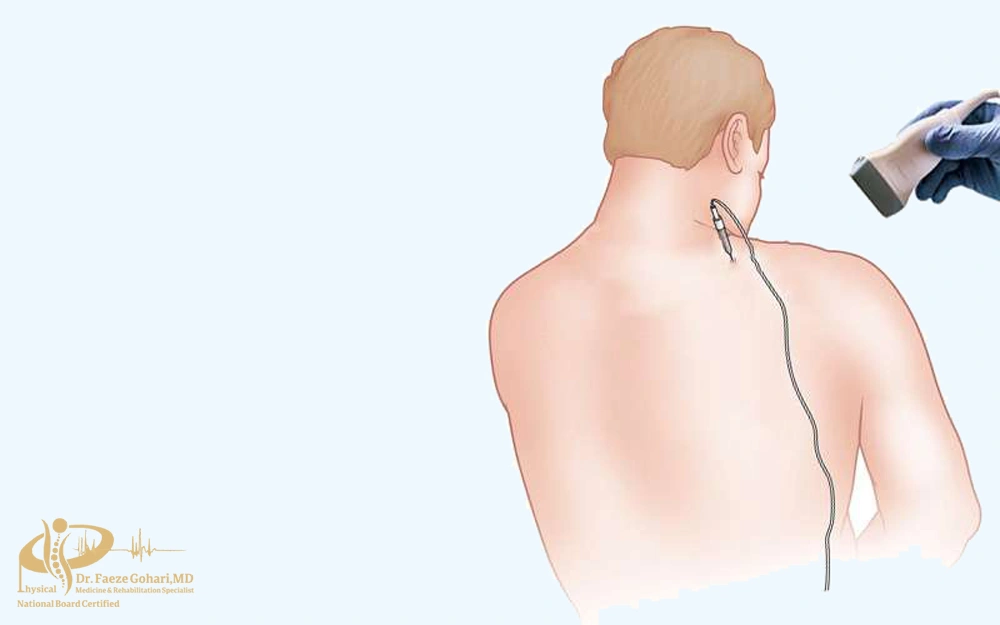

نحوه انجام بلوک عصبی ستونفقرات

بلوک عصبی ستون فقرات به دو روش اصلی انجام میشود: تزریق دارو و رادیوفرکانسی (RF). هر دو روش با هدف مهار انتقال پیامهای درد و کاهش التهاب بهکار میروند، اما در نحوه اجرا و مدت اثر تفاوت دارند. روش تزریقی بیشتر برای تسکین موقت و کمک به تشخیص منبع درد استفاده میشود، در حالی که روش RF معمولاً برای کنترل طولانیمدتتر درد انتخاب میگردد.

- بلوک با تزریق دارو

در این روش، پزشک با کمک تصویربرداری (فلوروسکوپی) سوزن ظریف را در کنار عصب یا مفصل موردنظر قرار میدهد و داروهایی مانند بیحسی موضعی یا کورتون تزریق میکند. این داروها التهاب را کاهش میدهند و انتقال پیامهای درد را بهطور موقت متوقف میسازند. این روش معمولاً با بیحسی موضعی انجام میشود و بهجز سوزش مختصر یا فشار خفیف هنگام ورود سوزن و تزریق دارو، درد قابل توجهی ندارد. خود تزریق معمولاً ۱۵ تا ۳۰ دقیقه طول میکشد و اثر آن از چند روز تا چند ماه باقی میماند.

- بلوک با دستگاه رادیوفرکانس (RF)

- در این روش، سوزن مخصوص به دستگاه RF متصل شده و در کنار عصب قرار میگیرد. سپس با ارسال امواج رادیوفرکانسی، انتقال سیگنال عصبی مختل میشود. این کار میتواند به دو صورت حرارتی (ایجاد حرارت و قطع طولانیتر پیامهای درد) یا پالسی (کاهش درد بدون آسیب دائمی عصب) انجام شود و اثر آن معمولاً چند ماه تا یک سال باقی میماند. ورود سوزن مشابه روش تزریقی است و بیمار ممکن است در حین فعال شدن امواج حرارتی کمی احساس گرما یا تیرکشیدن در مسیر عصب داشته باشد که قابل تحمل است و گاهی با آرامبخش کنترل میشود. مدت انجام آن حدود ۳۰ تا ۴۵ دقیقه است.